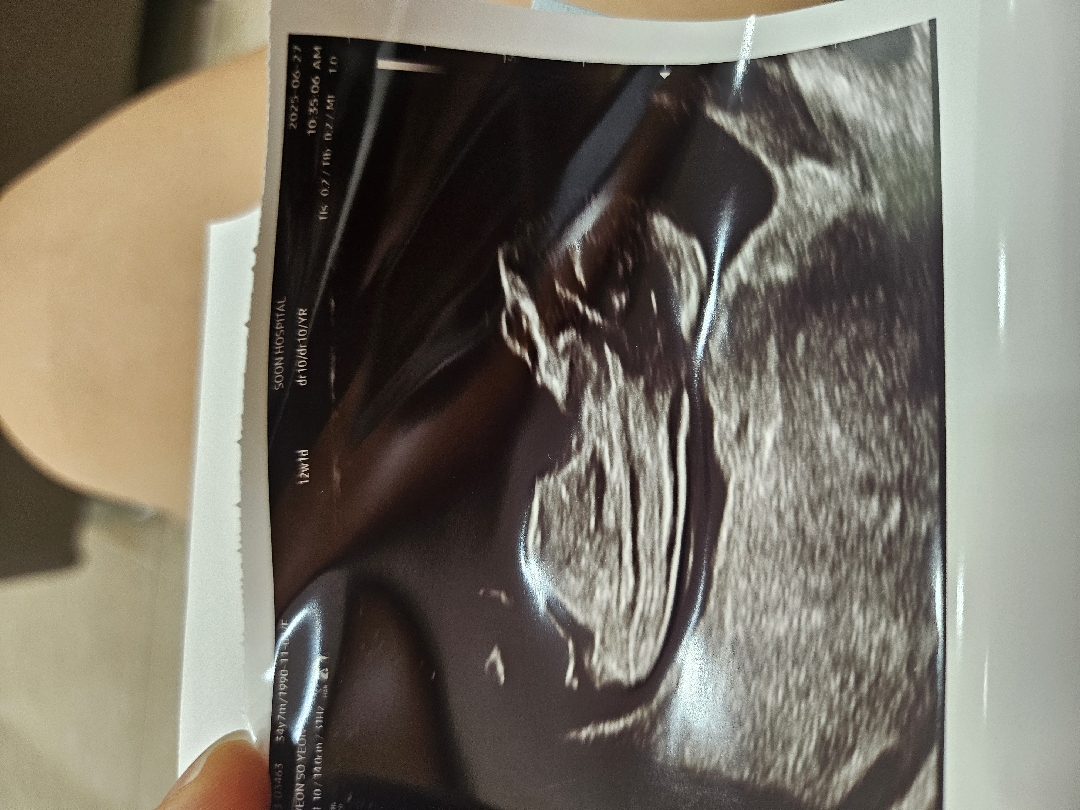

엊그제 병원다녀왔어용ㅎㅎㅎ 12주1일인데 각도법 궁금하네용 고수님들 도와주세요!!!